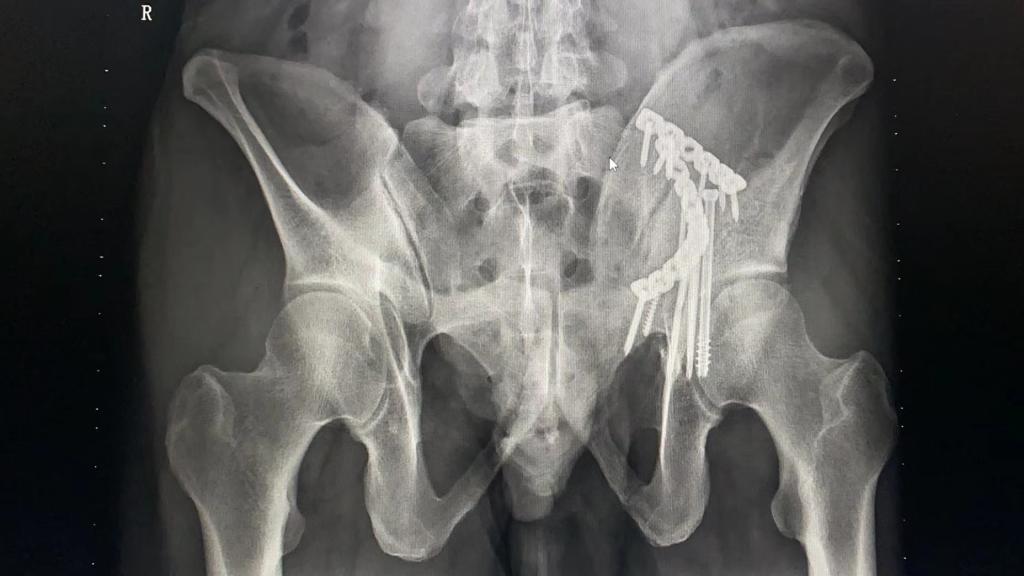

當天,段先生工作時不慎從高處墜落,被120救護車就近送至柳州市人民醫院醫療集團急診急救中心潭中分中心急救。完成初步檢查后,醫生判斷為髖臼雙柱骨折。髖臼骨折被醫療界認定為最復雜的骨折之一,特別是髖臼雙柱骨折意味著髖臼完全失去支撐,骨折復位固定失去參照,手術難度極高。為了讓段先生得到更好的治療,集團急診急救中心潭中分中心立即與總院取得了聯系。

隨后,柳州市人民醫院醫療集團總院立即開啟綠色轉診通道,創傷骨科迅速為段先生安排了床位,在科室手術團隊的共同努力下,為其順利實施了復雜的髖關節手術。11月初,段先生達到出院標準。面對柳州市人民醫院醫療集團的高效轉診和醫務人員的真誠溝通、貼心服務,段先生豎起了大拇指。出院后,段先生定期前來醫院復診。